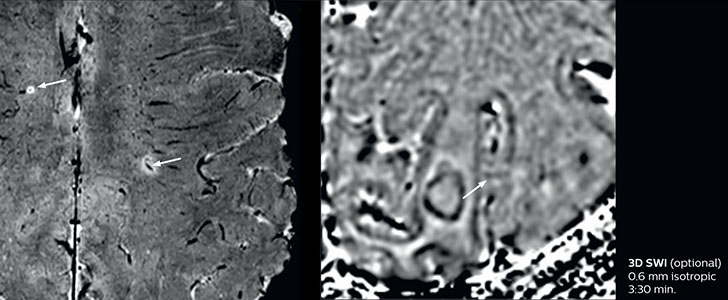

Fast MS protocol with optional sequences

The abbreviated MS protocol for brain is only around 9 minutes, so in case of suspected multiple sclerosis, one or two more advanced sequences may be added, such as PSIR (phase sensitive inversion recovery) or susceptibility-weighted sequences to help us make more confident diagnoses in these inflammatory cases.

In this example, the optional 3D multishot susceptibility weighted sequence with 0.6 mm isotropic voxels is 2 lesions with a central vein sign (arrows) and one lesion with a phase-rim sign (arrowhead). The total scan time, including SmartBrain and axial PD/T2 3mm, is 11:10 min. and is 18:30 min. with the optional 3D PSIR and 3D SWI multishot included.

“In multiple sclerosis patients, we increasingly include a multishot susceptibility sequence [3] in our routine cases, thanks to the shorter scan times. Our abbreviated MS protocol for brain is around 8 to 9 minutes, so we can ask for one or two additional sequences to visualize the central veins, or to get an additional contrast to better depict posterior fossa lesions. In cases of white matter lesions of unknown significance on FLAIR images, for example when we see high signal hyperintensities in the brain, we can add on more advanced sequences such as PSIR (phase sensitive inversion recovery) or susceptibility-weighted sequences to help us in distinguishing between MS and nonspecific or vascular abnormalities in these inflammatory cases.”